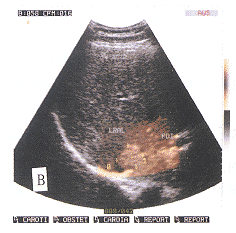

肝血管瘤是因为肝内小血管组织感染,肝组织局部坏死或肝内出血,血肿机化等原因造成肝内局部血循环停滞,血管海绵状扩张,静脉淤血膨大形成血管瘤。或因为肝内小血管发育异常,形成蜂窝状大小不一血窦,血窦间为纤维间隔,间杂血管和胆管〔1〕。因此病灶内血流极为缓慢或相对静止。CDFI对血流的显示是依据血流速度和角度的密切关系,低速血流及角度大于60°则CDFI敏感性降低。CDFI对肝血管瘤中的极低血流或相对静止的血流是不敏感的,本组中CDFI能显示的血流可能是来自于病灶外较粗静脉血管的分支(图1)。本组CDFI对病灶内血流显示率仅为22.47%。PDI是以能量方法显示血管内血流,仅与血管内红细胞等散射体数量有关,以能量信号作为成像参数,与单位面积内红细胞通过的数量及血流中红细胞的密度有关〔2〕,不依赖于声束与血管成角大小及检查时探头放置的角度。只要病灶中有极低速血流或红细胞产生运动都可以被PDI显示。PDI敏感性是CDFI的3~5倍〔3〕。本组中PDI能很敏感地显示部分病灶内低速血流。部分病灶内血流相对静止,但随呼吸运动,血窦内红细胞而产生运动,产生极低速血流;或因呼吸气屏气,腹腔压力增高,肝静脉血管内压力增高使血管瘤内血窦扩张,血窦内红细胞产生运动,这种细胞运动难以产生频移差,所以CDFI对之不敏感,而PDI则能敏感地显示,以充满型血流图表现即“繁星闪烁”征(图2)。部分病灶以点状、杆状或条状显示能量血流图。本组PDI对病灶内血流显示率高达96.6%。因而PDI对肝血管瘤的诊断较CDFI有很高的应用价值。

A图为CDFI显示病灶内血流为0级。

B图为PDI显示深吸气时病灶呈充满型能量图“繁星闪烁”征,血流分级Ⅲ级。

图2 血管瘤位于肝右前叶近第二肝门处,大小22mm×20mm